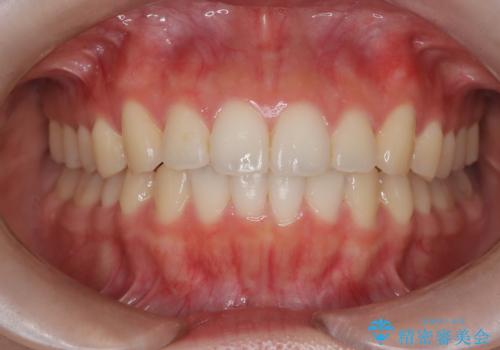

- 笑ったときに八重歯が見えることを主訴に来院されました。

下の前歯が一本足りない患者様でしたので、シミュレーションを作り、事前に患者様と治療ゴールのイメージをしっかり共有したうえでインビザラインを用いて治療を行っています。

奥歯を後ろのほうに動かすことで、前歯も少し下がることができ、矯正後の口元も満足していただきました。